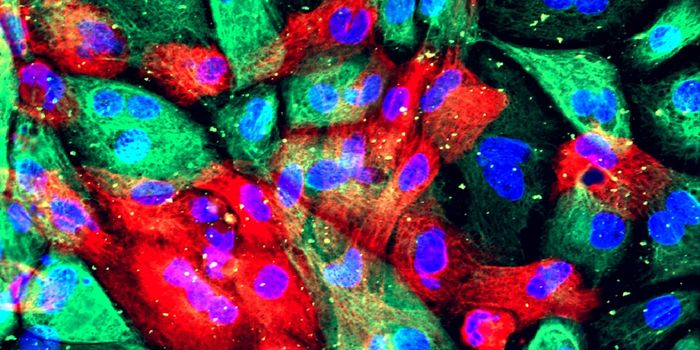

OCT 28, 2021CancerA family of proteins, known as transcription factors, regulate the biological process of converting DNA into RNA. T ...

OCT 25, 2020Cell & Molecular BiologyEwing sarcoma is a rare kind of cancer that tends to impact young people and occurs in bones or the tissue around them. ...

OCT 19, 2020CancerCancer is a disease characterized by DNA mutations. These mutations, while sometimes small, can cause havoc in a cell&rs ...